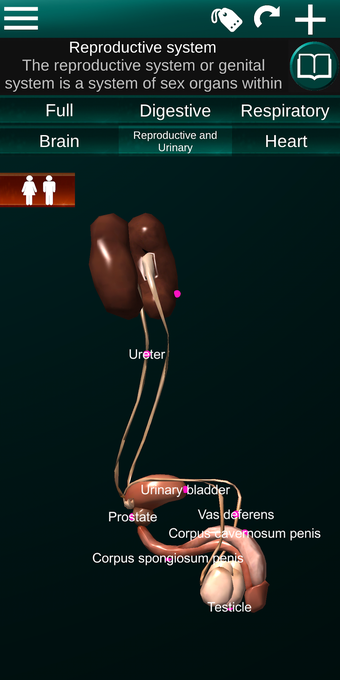

Diese Anwendung zeigt ein dreidimensionales Modell der menschlichen Körperorgane und eine Beschreibung aller von ihnen.

Sie können jedes Organ wie Herz, Gehirn, Lunge, Fortpflanzungssystem, Leber, Darm, Eierstock, Hoden, Magen, Niere usw. anfassen.

Sie ist für alle Menschen nützlich, auch für Studenten, da jedes Anatomieorgan in einer anderen Farbe dargestellt ist.

Sie können die App verwenden, um herauszufinden, welches die verschiedenen Körperorgane sind und welche Funktionen sie haben.